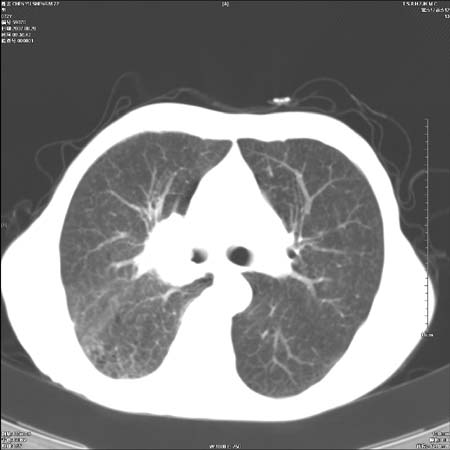

男性,72岁,既往肺结核,今复查。无前片对比。

右侧中央型肺癌伴中叶不张可能性大,建议增强扫描.右上肺陈旧性肺结核.慢性支气管炎伴肺气肿.右侧少量胸腔积液.

右侧中央型肺癌伴中叶不张可能性大,建议纤支镜检查.右上肺陈旧性肺结核.肺气肿。

典型右肺中心型肺癌

右侧中央型肺癌伴肺不张可能性大,建议增强扫描.右上肺陈旧性肺结核.慢性支气管炎伴肺气肿.右侧少量胸腔积液.

右肺中心型肺癌

右侧中央型肺癌.上肺陈旧性肺结核.

1右侧中央型肺癌伴中叶不张2右侧少量胸腔积液3右上肺陈旧性肺结核

1.右肺中心性肺癌并右肺中叶综合征2。右侧胸腔少量积液3。右肺上叶结核球已钙化,4。慢支伴肺气肿

右侧中央型肺癌伴中叶不张可能性大,建议纤支镜检查.右上肺陈旧性肺结核.肺气肿。

右侧中央型肺癌伴中叶不张可能性大,建议增强扫描.右上肺陈旧性肺结核.慢性支气管炎伴肺气肿.右侧少量胸腔积液.

右侧中央型肺癌伴中叶不张

右肺中央型肺癌伴右肺中叶不张。

右上肺陈旧性肺结核。

支持右肺中心型肺癌并中叶不张,右上肺陈旧性肺结核钙化,右侧少量胸腔积液。

支持右侧中央型肺癌伴中叶不张可能性大,建议增强扫描.右上肺陈旧性肺结核.慢性支气管炎伴肺气肿.右侧少量胸腔积液.

支持 1右侧中心型肺癌伴中叶不张2右侧少量胸腔积液3右上肺陈旧性肺结核4双肺局限性肺气肿

1,右侧中央型肺癌.

2,右上肺陈旧性肺结核.

1.右侧中央型肺癌伴中叶不张,建议纤支镜检查.

2.右上肺陈旧性肺结核.

3.肺气肿。

4.右侧少量胸腔积液.

右侧中央型肺癌伴中叶不张并纵隔淋巴结增大,建议增强扫描.右上肺陈旧性肺结核.慢性支气管炎伴肺气肿.右侧少量胸腔积液。

右肺中心型肺癌并肺不张,陈旧性肺tb.慢支,肺气肿.

陈旧性肺结核.慢性支气管炎伴肺气肿,中央型肺癌伴中叶不张。

右侧中央型肺癌伴中叶不张可能性大;右上肺陈旧性肺结核.慢性支气管炎伴肺气肿

陈旧性结核是存在,但真正致命的却是右侧中心型肺癌。